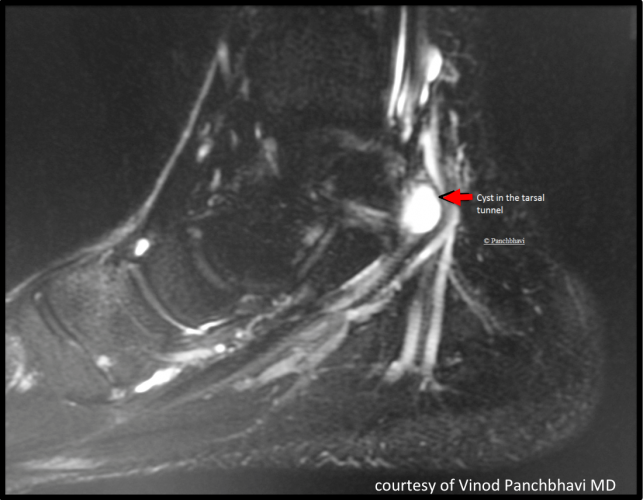

Syndrome Du Canal Tarsien Temoignage. Syndrome du Tunnel Tarsien Symptômes et Soins La douleur, le symptôme le plus fréquent du syndrome du canal tarsien, crée généralement une sensation de brûlure ou de fourmillement, survenant en station debout, à la marche ou lorsque la personne porte un type de chaussures spécifique. Il peut s'agir d'une cause anatomique, comme un os, un kyste, des varices, qui exerce une pression sur le nerf tibial postérieur.Les blessures au pied ou à la cheville, les inflammations, ou encore l'arthrose peuvent également entraîner ce syndrome.

Le syndrome canalaire du pied Podexpert. Il peut s'agir d'une cause anatomique, comme un os, un kyste, des varices, qui exerce une pression sur le nerf tibial postérieur.Les blessures au pied ou à la cheville, les inflammations, ou encore l'arthrose peuvent également entraîner ce syndrome. Malgré son importance, il reste sous-diagnostiqué, contribuant à diverses douleurs du pied telles que les douleurs de talon et de voûte plantaire.